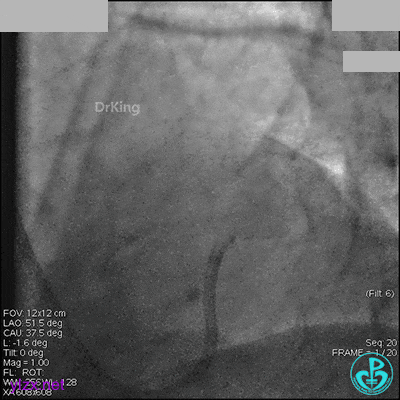

1周后再次上台,右冠脉3级血流,3段局限性严重狭窄,内膜模糊,应该是上次操作夹层遗留下的血肿。

先处理前降支开口严重狭窄并顺利植入前降支到左主干支架。